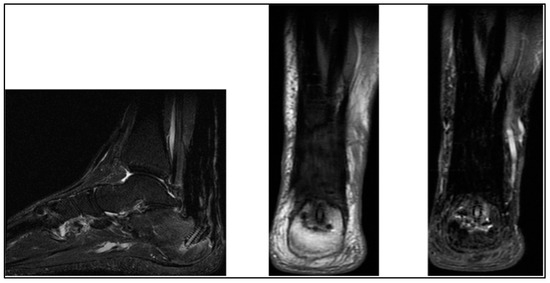

| Graft Signal Intensity | Near-normal on T1, mild on PD-FS | Near-normal on T1, mild on PD-FS |

| Fiber Orientation | Well aligned, reduced edema | Well aligned, reduced edema |

| Bone Block Incorporation | Partial bridging, stable positioning | Partial bridging, stable positioning |

| Soft Tissue Reaction | Minimal scar tissue seen | Minimal scar tissue seen |

| Graft Integrity (MRI) | Normal T2 signal, intact fibers | Normal T2 signal, intact fibers |

| Bone Block Union (X-ray) | Complete union, no hardware issues | Complete union, no hardware issues |